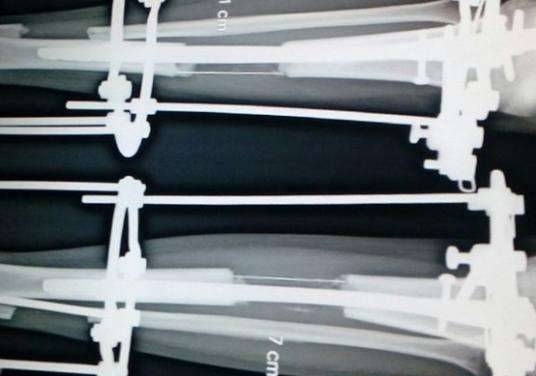

▼增高手术其实是一种将患者的腿骨「打断」,然后在腿部外面装上支架固定,直到患者的腿骨自行愈合时,腿骨就会长成自己所需要的长度。在理论上,这听起来非常简单,然而真正实行时,却是一个极度繁琐和高风险的手术。